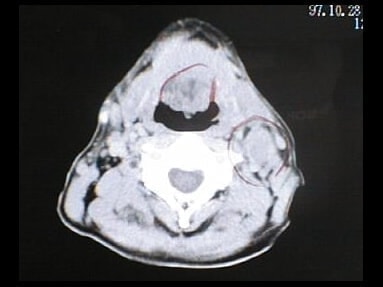

末期がん宣告時と末期がん消滅時の診断画像比較

ここでは、末期がんと宣告された時のCT&MRI画像と、その約3か月後の末期がん消滅時の画像を比較して頂けます。(写真左が「末期がん宣告時の画像」、写真右が「末期がん消滅後の画像」)

MRI画像比較

入院当時MRI画像③

入院3か月後癌消滅MRI画像③

入院当時MRI画像④

入院3か月後癌消滅MRI画像④